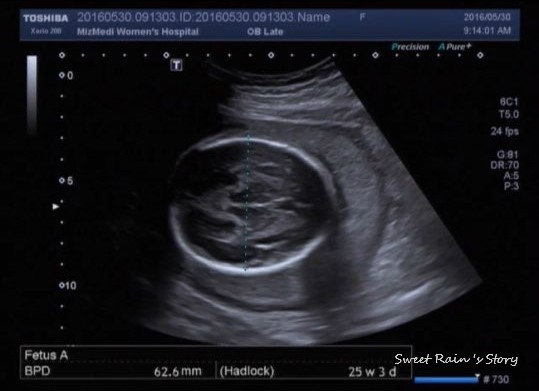

임신 25주 - 임신성당뇨검사, 임신성당뇨재검사, 임당검사

이번주 월요일 남편이랑 함께 임신성 당뇨 검사를 하러 미즈메디 병원에 갔지요. 저의 주치의 쌤은 25주에 ...

임신 25주 - 정기검사, 25주차 증상

울 사랑하는 복덩이가 우리 부부에게 찾아 온지도 벌써 25주가 되었어요. 24주차에는 살짝 피가 비쳐서 응...